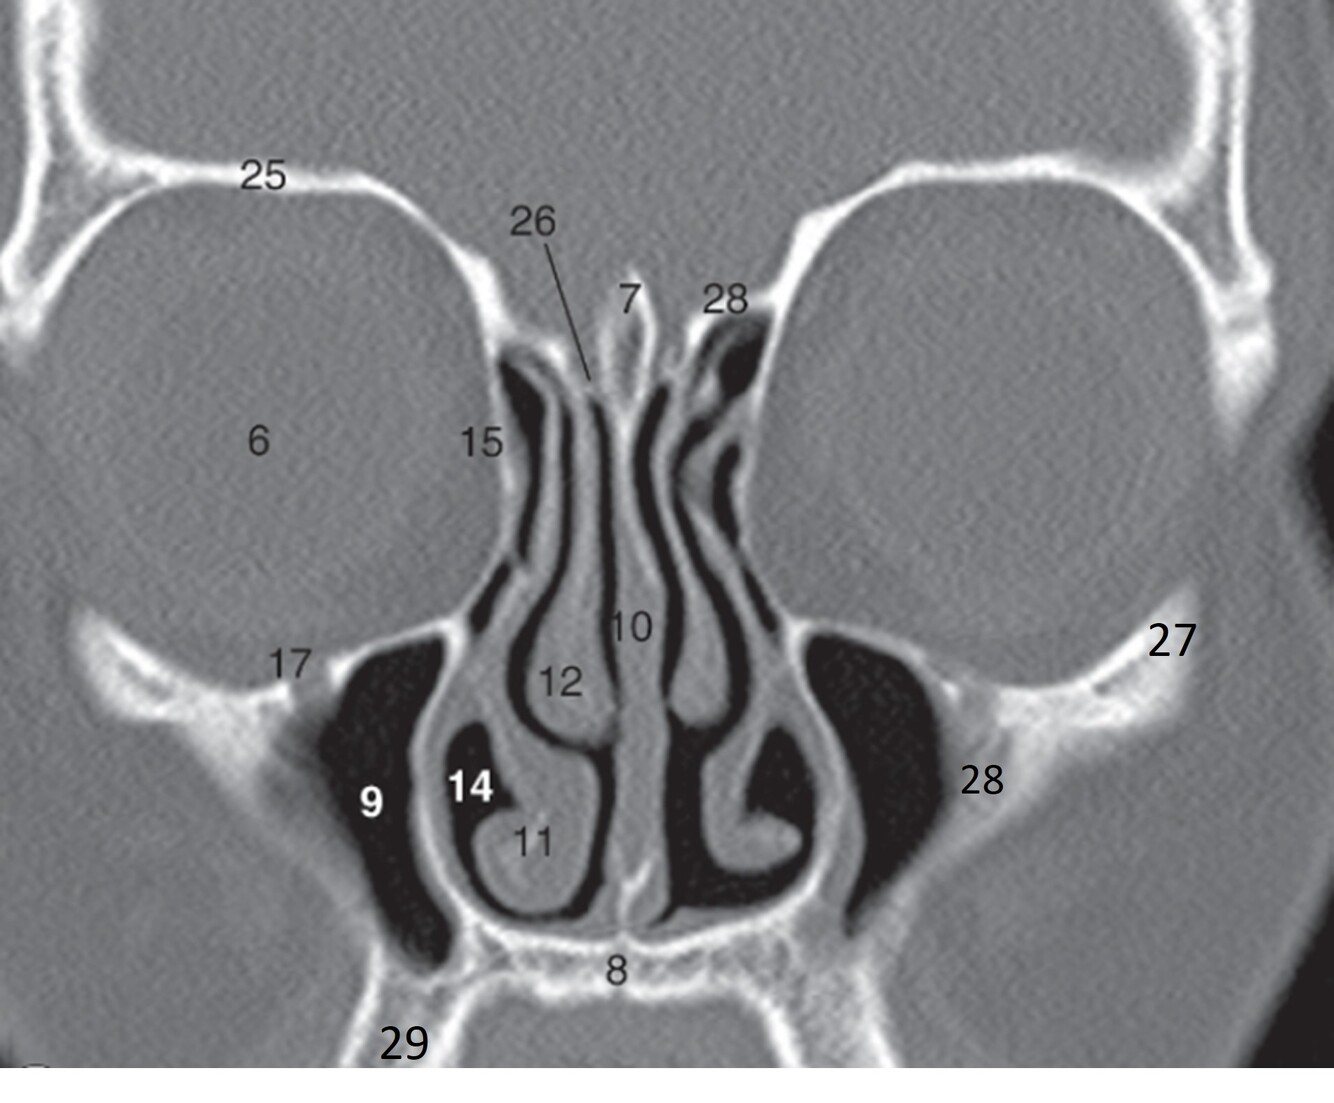

6

Label 7-12

A

7=Crista Galli (Ethmoid)

8.=Hard palate (Maxilla)

9=Rt. Maxillary sinus

10=Nasal septum

11=Rt. Inferior nasal concha

12=Rt. Middle nasal concha

How well did you know this?

7

Label 14,15,17,25,26

14=Rt. Inferior nasal meatus

15=Rt. Lamina papyracea (Ethmoid)

17=Rt infraorbital foramen (Maxilla)

25=Rt Orbital roof (frontal bone)

26=Rt Cribriform plate (Ethmoid)

8

Label 27-29

27=Lt Zygoma

28=Zygomatic process (Lt Maxilla)

29=Alveolar process (Rt Maxilla)